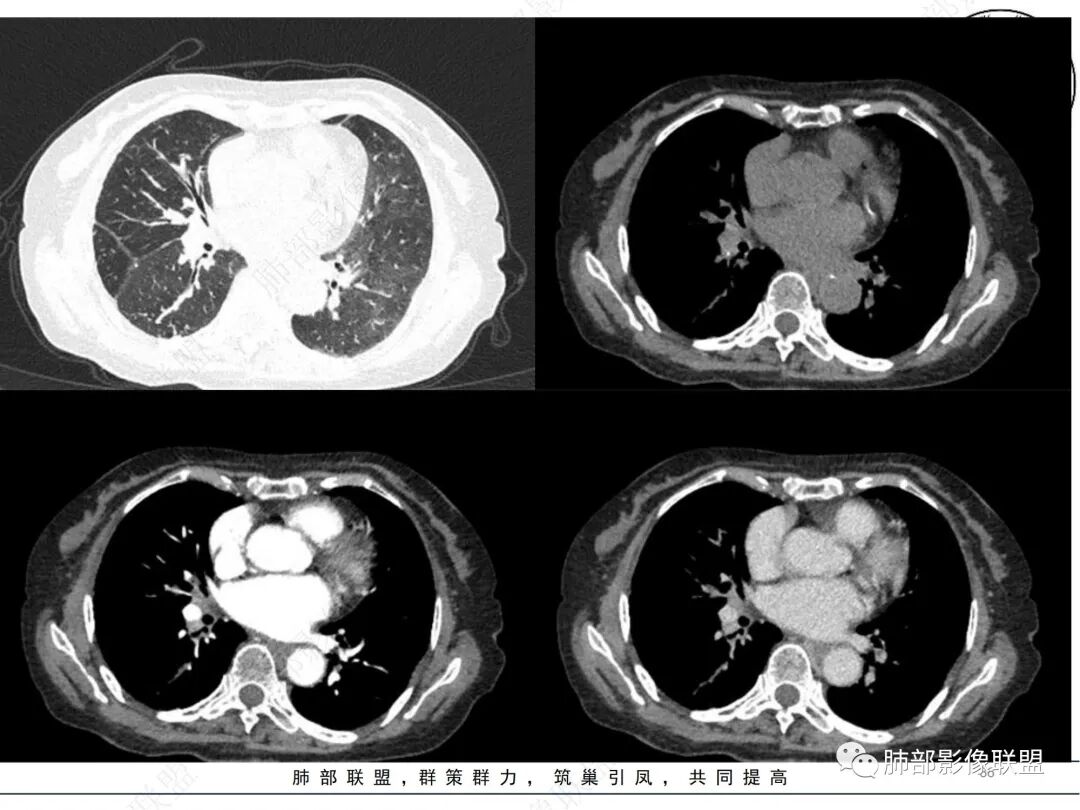

2. CT示右肺上叶多发斑片状实变影,结节影,集群散落,夹杂条索影,边界可分辨,有沿支气管血管束分布趋势,可见树芽征。病灶新旧不等、密度不均。右上叶支气管壁不均匀节段性增厚狹窄,斑点状钙化。纵隔旁部分肺组织含气不良,并显示轻度扩张支气管。病灶邻近胸膜增厚,轻度强化。

3.余双肺显示马赛克灌注、轻度气肿。双肺散在微小实行密度结节影,边界清楚。

4.纵隔多发增大淋巴结,部分融合、钙化。

成簇分布斑片影、结节影、树芽征,边界较清楚,新旧不等,节段性支气管壁增厚伴钙化,管腔狭窄,纵隔及肺门淋巴结增大钙化等都较符合“继发性肺结核、支气管内膜结核”诊断。